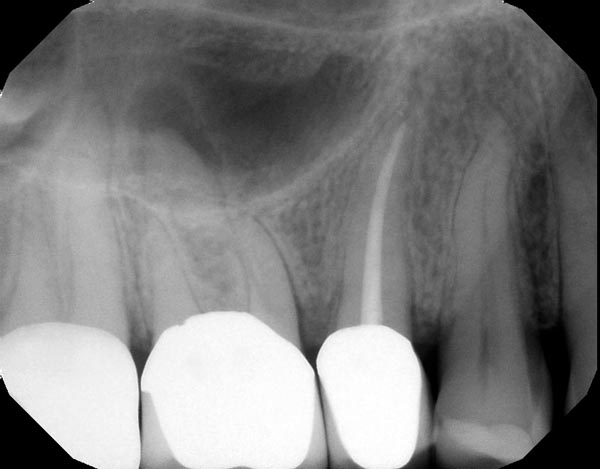

Fig. 4a: Preoperative image of tooth #31 with an irreversible pulpitis. The mesial roots have a subtle “S”-shaped curve and the preoperative working length was estimated to be 23mm. It was also assumed preoperatively that the MB and ML canals would be in close approximation or connected in the apical half of the root. This anatomy requires a flexible and efficient instrument with a good degree of torque strength. Fig 4b: Instrumentation was completed with Vortex Blue from Dentsply Sirona, a 500rpm, constant tapered file with excellent cutting efficiency. The postoperative image shows the files were able to follow the natural curves of the canal in multiple planes as the MB and ML canals joined in the apical half of the root.

Fig. 4a

Fig. 4b